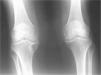

En el ingreso en nuestra consulta externa fue atendido por un brote de monoartritis en la rodilla derecha que mejoró tras artrocentesis e infiltración corticoidea. Radiológicamente, en el ingreso presentaba CCA en ambas rodillas, más acentuada en la rodilla derecha, con discreto pinzamiento de interlínea articular interno femorotibial. No se detectó CCA en las muñecas ni en la sínfisis púbica.

Destaca en la evolución de sus rodillas, tras 5 años de tratamiento, progresión de sus lesiones radiológicas (figs. 1 y 2). Adicionalmente, se realizó el estudio familiar mediante radiografías de rodillas a los familiares vivos de primer grado: su madre, 2 hermanas (de 35 y 32 años, respectivamente) y un hermano (de 27 años), y sólo se detectó CCA en su madre.

Radiografía anteroposterior de rodillas en su evolución a los 5 años en la que se aprecia pinzamiento articular femorotibial interno, esclerosis subcondral y osteofitosis marginal más marcado en rodilla derecha, aumento de intensidad y extensión de las calcificaciones en cartílagos y meniscos de ambas rodillas e imagen quística en cara interna 1/3 superior de tibia derecha.